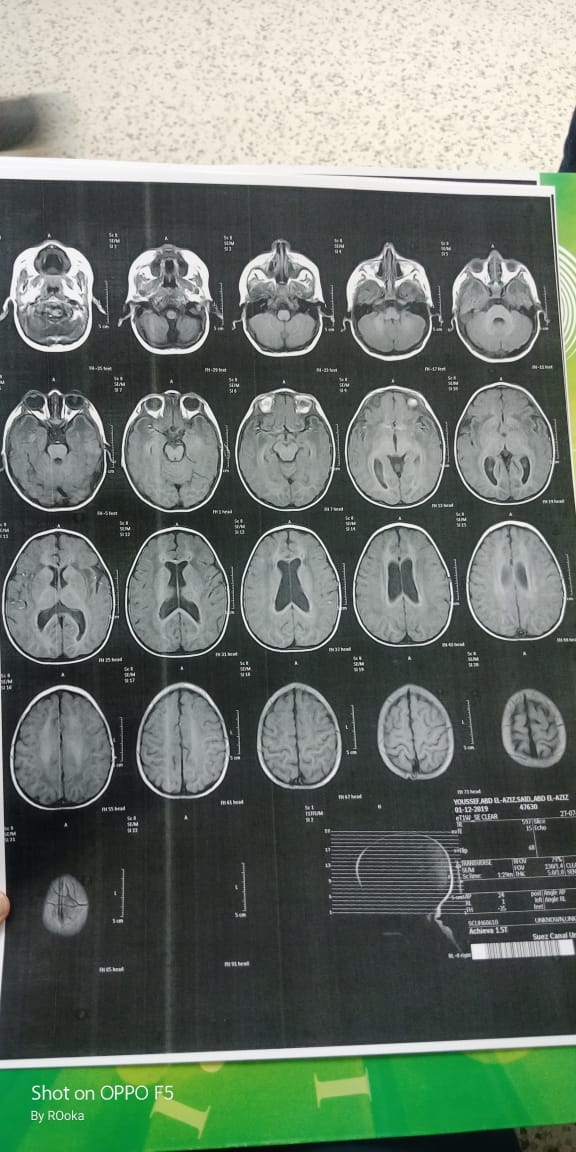

وأضاف عبد العزيز، في تصريحات خاصة لـ القاهرة 24: اكتشفنا مرض يوسف وهو عنده 6 شهور، طلع عنده نقص في المادة البيضاء، ونقص في الأكسجين، مع تآكل في القشرة المخية.

وأكد أن طفله فاقد للحركة والكلام حاليًا، مع تمدد حجم الدماغ، نتيجة معاناته من اختلالات عصبية، التي تنشأ عن المرض، معقبًا: الطفل يحتاج لجهاز طبي يساعد على تخفيف حدة الأعراض، وفقًا لاستشارة الأطباء.